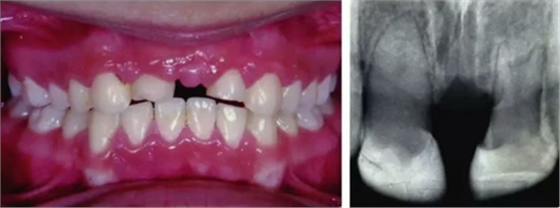

事故發(fā)生四周后,這名男孩接受了正畸醫(yī)生的檢查??谕鈾z查顯示沒(méi)有軟組織損傷,可能是因?yàn)闄z查較遲??趦?nèi)檢查也沒(méi)有撕裂傷或牙槽骨骨折。臨床檢查顯示,患者為安氏II類錯(cuò)合,開(kāi)牙合,下頜間隙不足及擁擠。正畸治療的目的是改善II類錯(cuò)合畸形并通過(guò)拔牙改善下頜擁擠。在完成影像和臨床檢查后,選擇拔除下頜第二前磨牙。由于上頜切牙的缺失,我們決定在正畸拔牙時(shí)將下頜第二前磨牙移植到上頜切牙的位置。

初步正畸牽引嵌入的上頜側(cè)切牙并重新獲得切牙空間。上頜側(cè)切牙的預(yù)后顯示有嚴(yán)重的牙根吸收。因此需要拔除上頜側(cè)切牙(圖3)。

圖3. 影像學(xué)顯示上頜側(cè)切牙牙根吸收